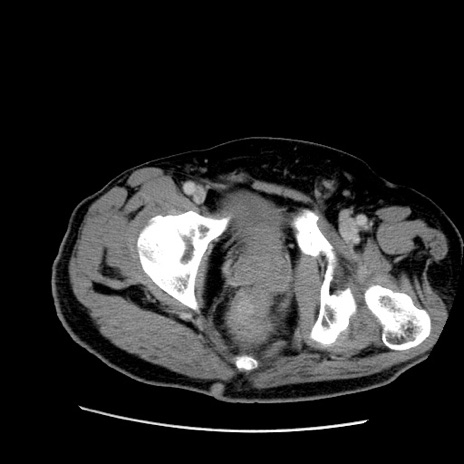

症例22(横断像)

【症例】50歳代男性

【主訴】腹痛

【現病歴】AVMからの被殻出血のため回復期リハ病棟入院中。 本日午後3時頃急に下腹部痛が出現した。

【既往歴】AVM、被殻出血、虫垂炎、高血圧

【身体所見】意識晴明、左半身不全麻痺、会話の理解は良好、36.5°C、腹部:膨隆、全体に板状硬、下腹部正中に圧痛点あり、反跳痛-、筋性防御不明、右下腹部にope scar

【データ】WBC 9400、CRP 0.06